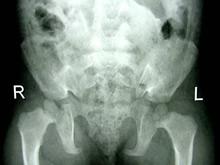

软骨发育不全(achondroplasia)又称胎儿型软骨营养障碍(chondrodystrophia fetalis),软骨营养障碍性侏儒(chondrodystrophic dwarfism)等。是一种由于软骨内骨化缺陷的先天性发育异常,主要影响长骨。临床表现为特殊类型的侏儒-短肢型侏儒。